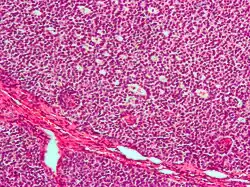

- ziarniszczak – nowotwór złośliwy, występuje głównie w okresie postmenopauzalnym. Cecha patomorfologiczna: ciałka Call-Exnera.